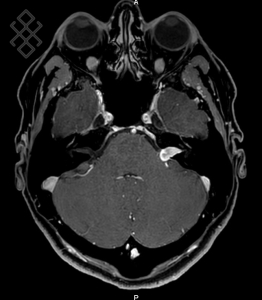

IRM des Conduits Auditifs Internes (CAI)

Pas d'indications